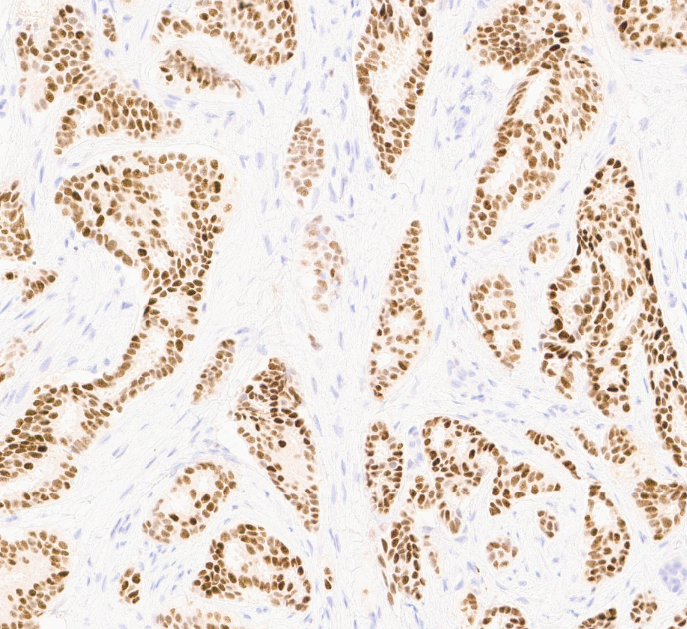

Positive stains

- Luminal

- Triple negative

- High molecular weight basal cytokeratins: CK5/6, CK14, CK17 (Clin Cancer Res 2007;13:4429)

- EGFR (J Lab Physicians 2015;7:79)

- TRPS1 (positive in 86% of triple negative and metaplastic carcinomas)

- GATA3 (nonmetaplastic: 51%, metaplastic: 21%)

- HER2 enriched

- Reference: Mod Pathol 2021;34:710